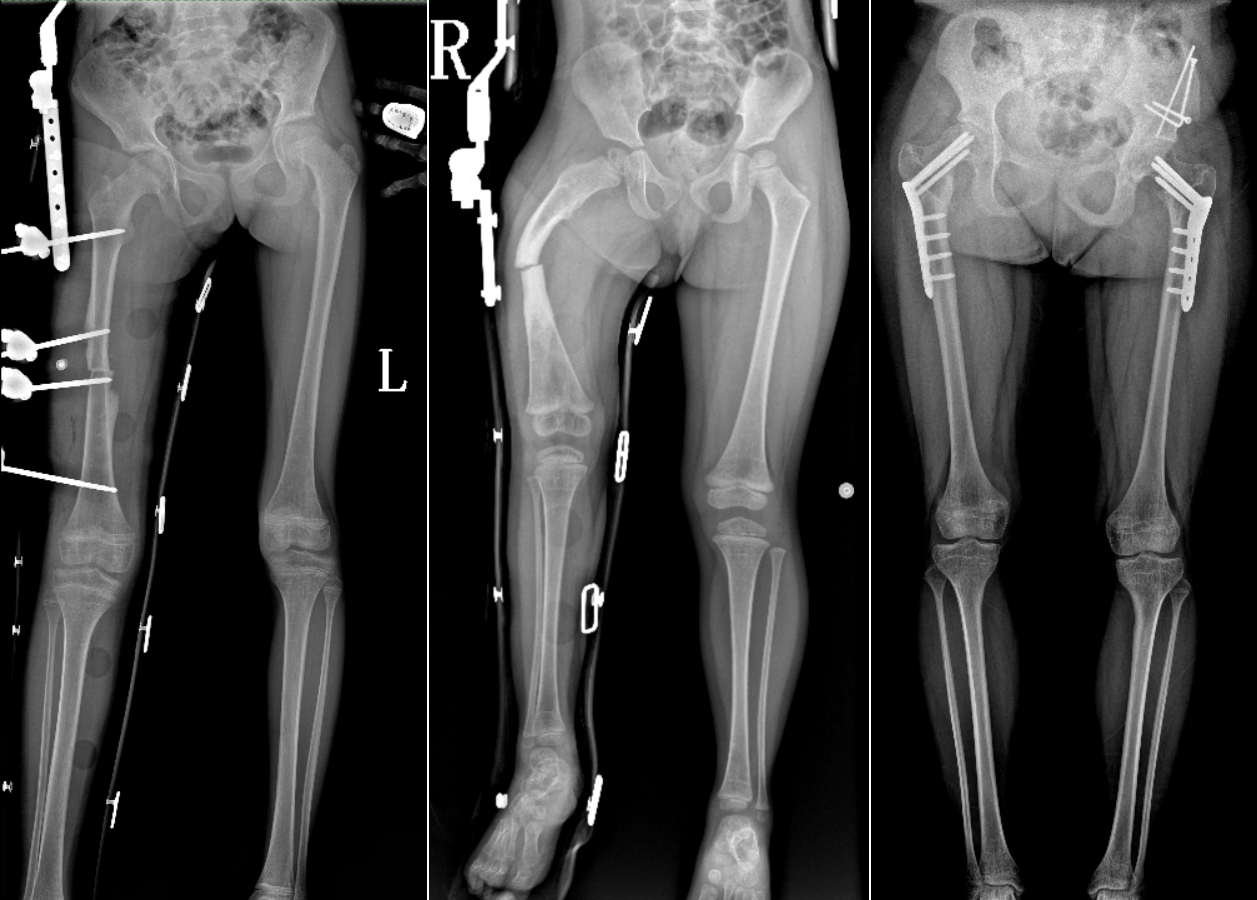

DR是臨床骨科的重要檢查手段之一。在骨科檢查中,脊柱矯形、長骨骨折、腰椎退行性病變等,需要采集脊柱、下肢全景圖像,輔助醫(yī)生臨床診斷,從而制定科學(xué)的治療方案,普愛醫(yī)療的大視野平板動態(tài)DR就像是一座橋梁,連接起現(xiàn)代醫(yī)療技術(shù)與當?shù)厝嗣竦尼t(yī)療需求。

普愛醫(yī)療自主研發(fā)的大視野平板動態(tài),采用17"*34"的有效視野,一次曝光即可得到全脊柱或全下肢影像。相較于多張攝影再軟件拼接的DR設(shè)備,PLX8600解決了拼接圖像存在密度不均勻,拼接處圖像配準和放大效應(yīng)等問題,給臨床帶來了真正的大視野影像解決方案。

除了常規(guī)靜態(tài)攝影外,PLX8600的大平板具備動態(tài)透視和點片功能,能夠很好地觀察復(fù)雜部位病灶,有效地抓取關(guān)鍵幀,降低患者多次攝片的概率。如:全脊柱狀態(tài)評估、長骨關(guān)節(jié)活動度、下肢靜脈造影瓣膜功能評估、消化道功能評估、脊髓造影等更多大視野臨床應(yīng)用,“多面手”都能輕松應(yīng)對。